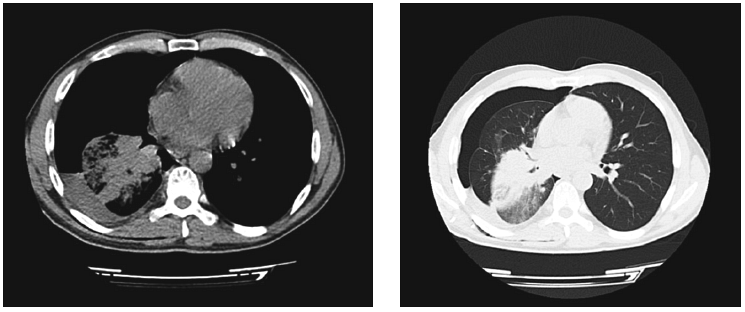

При цитологическом исследовании пунктата обнаружены клетки аденокарциномы. По данным выполненной МСКТ, имелись признаки периферического образования правого легкого с метастатическим поражением лимфатических узлов корня легкого, диффузный пневмосклероз, малый гидроторакс справа (рис. 3, 4).

Рис. 3. Рентгенологическая картина пациента М. при первичном обращении (выпот в плевральной полости) и после дренирования плевральной полости (наличие опухоли)

Рис. 4. КТ-картина образования правого легкого с выпотом в правой плевральной полости у пациента М.